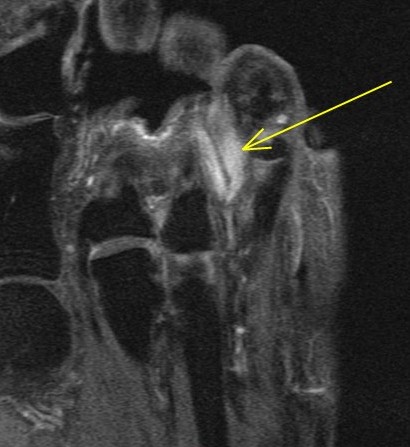

75 y/o male with toe mass.

Proven. Non painful. Mass of the skin at the base of the fourth toe. Patient sought medical attention due to the presence of the mass rather than symptoms. Last hidden image is enhanced. The disorder is rare. Reference article.

Nodular Localized Cutaneous Amyloidosis